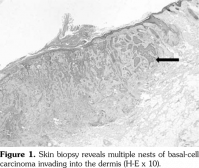

However, two years after the diagnosis of basal-cell carcinoma, the patient was re-admitted to the hospital due to complaints of feebleness, palpitation and cough lasting for 10 days. Laboratory analysis showed an increased white blood cell count of 20x109 L (NR 4-10x109/L), decreased red blood cell count of 1.28x1012/L (NR 3.5-5.0x1012/L), and platelet count of 45x109/L (NR 100-300x109/L). Serum electrophoresis revealed monoclonal protein of 68.24%. The urinary lambda (l) light chain was 0.186 (NR <0.05). Bone marrow biopsy revealed diffuse fibrosis with collagen deposition, heavy infiltration of neoplastic plasma cells (CD138, PC positive), and l light chain restriction (Figure 2-4) with a total ratio of 66% for original and naive plasma cells. Hence, the diagnosis of l plasmacytic leukemia was confirmed. However, our patient rejected to undergo further evaluation and treatment due to personal reasons.